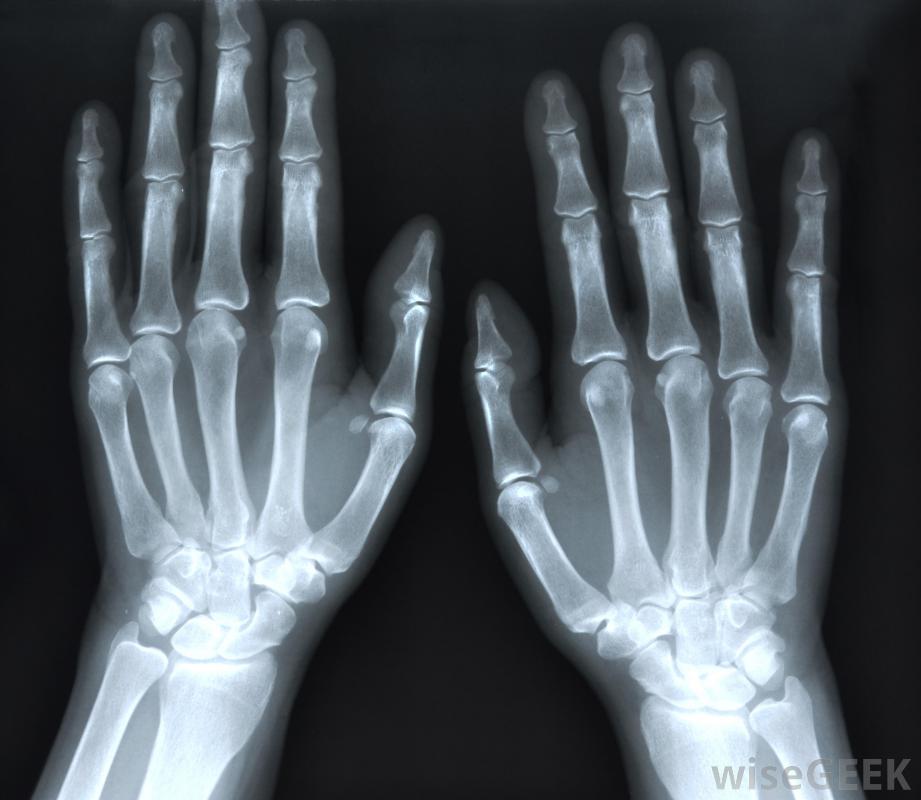

骨刺和關節炎可以通過X光片診斷。